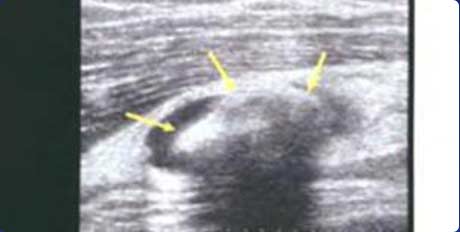

三、准确检测不同形态痛风石 提供精准治疗临床依据

超声图像中出现的以高回声为主的高低回声混杂的团块即为痛风石,一般表现为高回声、不均质、界限不清楚、边缘可见液性暗区,可伴有声影。超声通过对痛风患者皮下组织、软骨、滑囊、韧带等不同部位痛风石的不同表现形式(滑膜结节厚度、强回声团状数量、回声是否伴声影)的清晰观察,能对痛风石进行区分(软性痛风石或硬性痛风石),帮助制定患者的个体化、针对性治疗方案。

回声伴声影

膝关节髌上囊扩张积液,可见团状强回声,并伴声影

高回声团

关节横纵扫描图像,尿酸盐沉积形成略高回声团块-痛风石